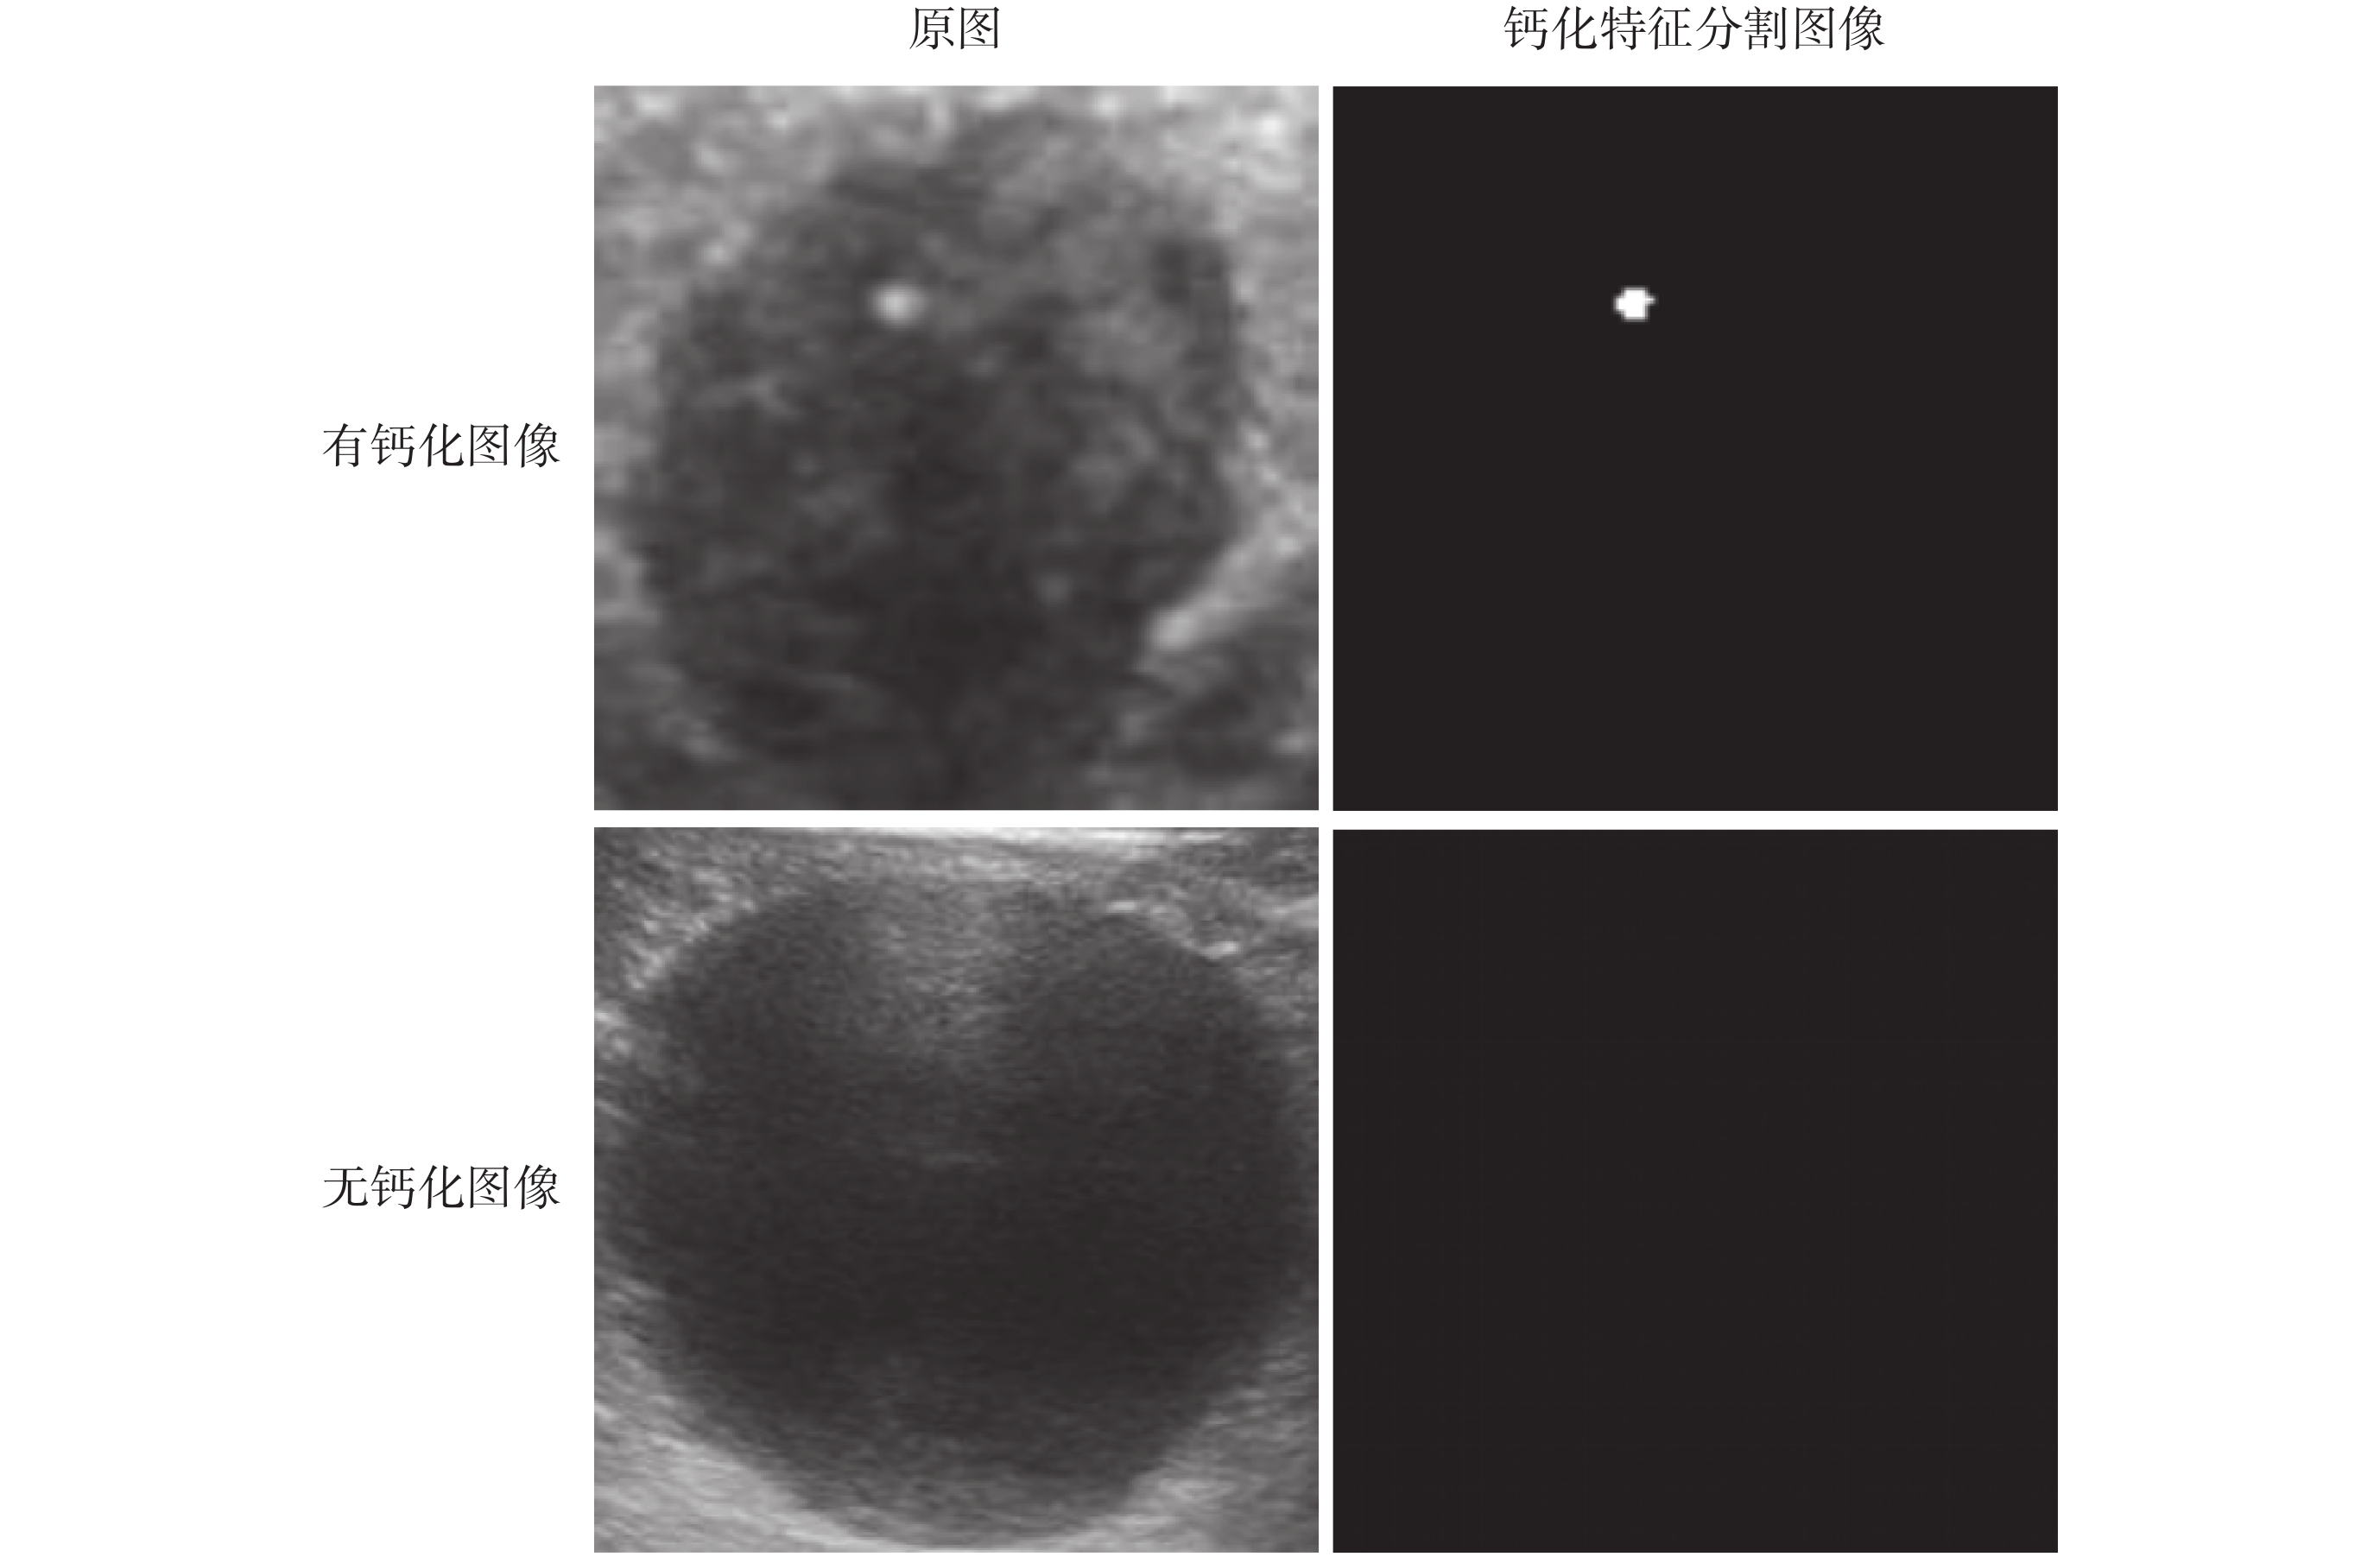

本文采用標定的鈣化點特征作為標簽,即特征模板為分割出鈣化特征的二值化圖像,如圖 7 所示,有鈣化圖像鈣化區域像素值為 255,其他區域像素值為 0;如果是無鈣化圖像,其對應的二值化圖像將全黑。

圖7

原圖及其對應標簽圖像

Figure7.

The original image and its corresponding label image